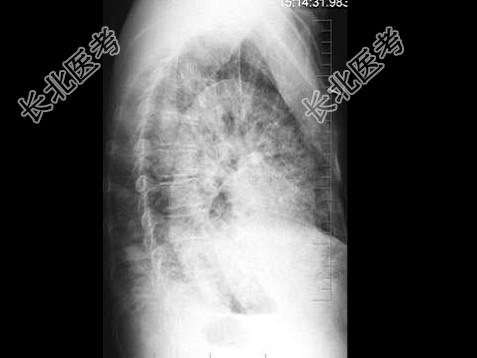

- 单项选择题男,56岁, 痰中带血1月余,X线检查如图, 最可能的诊断是 ( )

A、两肺炎症

B、肺转移瘤

C、血行播散型肺结核

D、细支气管肺泡癌

E、矽肺